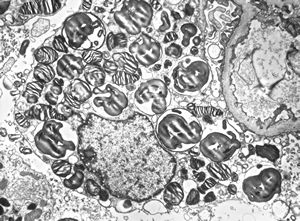

M,2y. | nephroblastoma (Wilms tumor)